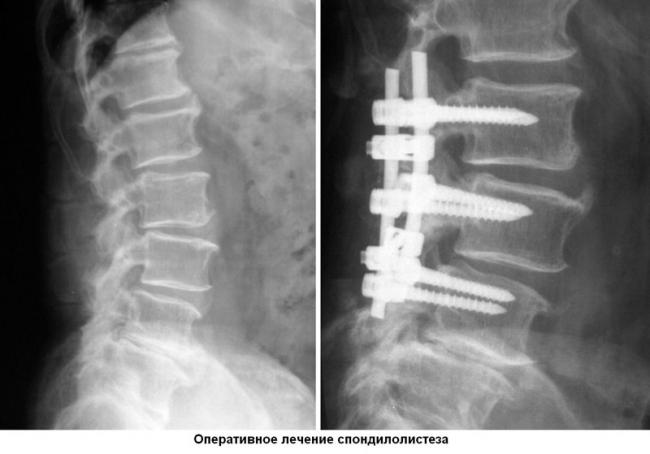

Оперативное вмешательство

К хирургической операции прибегают в том случае, если патология на 2 стадии и позднее. Чрезмерное смещение позвонка опасно сдавливанием спинного мозга, поэтому провести декомпрессию стоит как можно скорее. Вмешательство позволит также стабилизировать позвоночник.

Основным популярным способом является лапароскопия. Она отличается минимальной травматичностью и небольшими осложнениями после операции. Через небольшой разрез запускается зонд, который обеспечивает видеосъемку для полной видимости. В процессе не задеваются мягкие ткани, волокна мышц или связки, а значит кровотечение небольшое. После операции пациент может как можно скорее вернуться к нормальной жизни.

Пораженный позвонок замещается вентральной пластиной, или фиксируется винтами, замещается титановыми имплантами. Подбирается вид материала и подходящий вариант индивидуально, исходя из особенностей развития болезни.

Оперативное вмешательство назначается только при наличии показаний